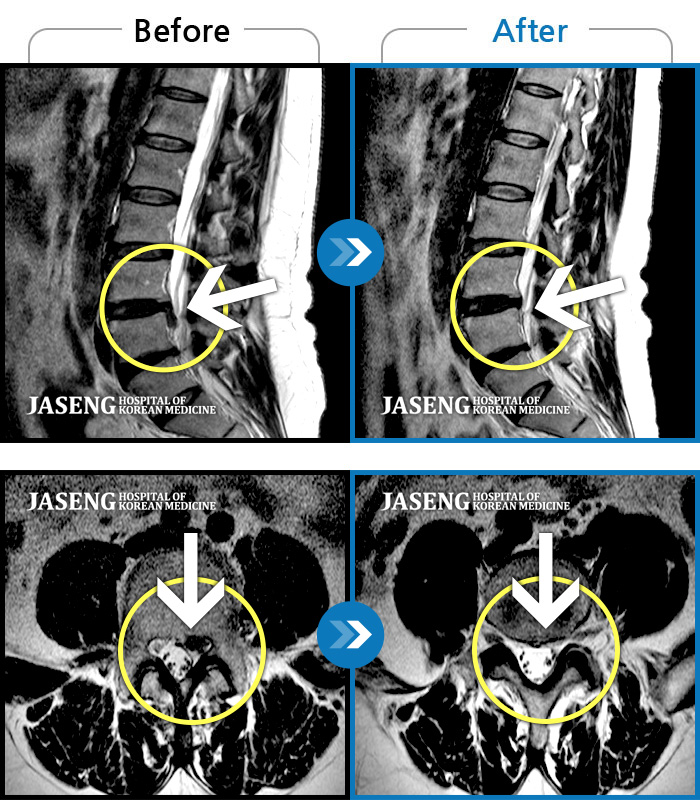

허리디스크

해운대 · 김상돈 원장

허리가 찌릿찌릿하고 찢어질 것 같은 통증

촬영시기

2024.01.08 ~ 2025.08.12

2025.08.29